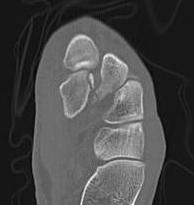

CT

Dorsal subluxation of the metatarsal